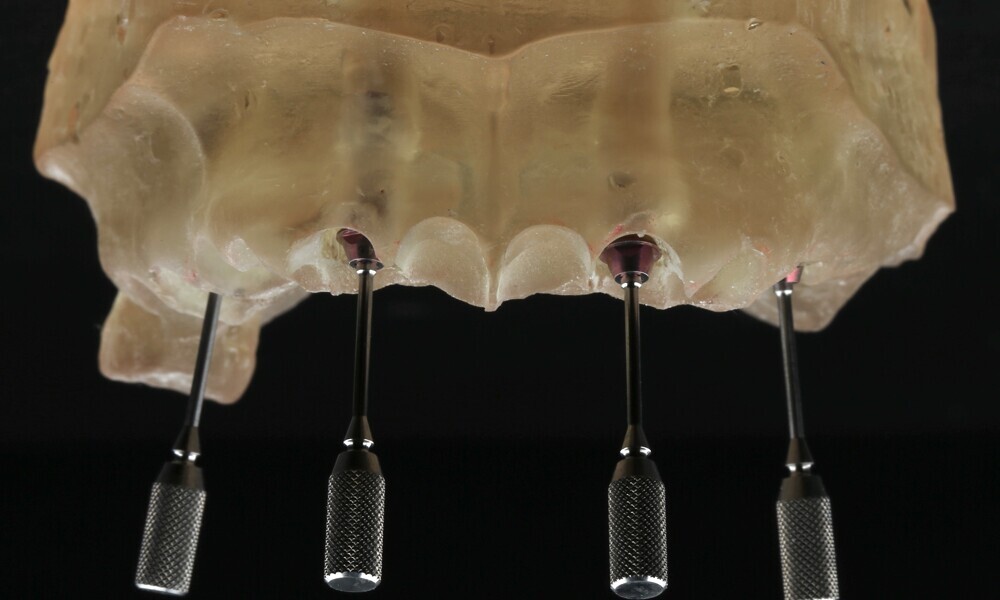

Compromised maxillary dentition treated with Straumann Pro Arch and a digital workflow